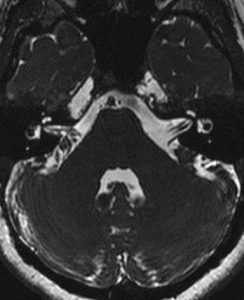

Что показывает МРТ мосто-мозжечкового угла

Мостомозжечковый угол — это маленькая область в головном мозге человека, которая ограничивается мостом и продолговатым мозгом. В данной зоне пролегают черепно-мозговые нервные окончания (лицевой и преддверный нерв).

В случае развития у человека ряда патологических процессов (онкологические патологии, воспалительные заболевания и т.п.), в мостомозжечковом угле будут наблюдаться выраженные поражения нервов. Это может стать весомым поводом для обращения к врачу и назначения МРТ мосто мозжечкового угла.

Особенности подготовки и проведения исследования

МРТ головного мозга не требует от пациента каких-либо серьезных подготовительных мер. Несмотря на это, перед процедурой человеку нужно будет снять все металлические предметы, в том числе украшения. МРТ мосто мозжечкового угла выполняется с помощью мощного томографа. При этом процедура сканирования должна иметь мощность воздействия магнитного поля не менее 1,5-2 Тл. Для получения максимально точной клинической картины, сканирование может выполняться в двух режимах. Общая длительность процедуры составляет 15-30 минут. В том случае, если у человека будут весомые показания, МРТ мосто мозжечковых углов ему может быть проведено с использованием контраста.

Расшифровка результатов

Расшифровкой результатов МРТ головного мозга занимается врач-диагност. При этом, наиболее часто у пациентов обнаруживаются онкологические патологии мостомозжечкового угла и нарушения кровообращения в сосудах. Информация о результатах, а также заключение о проведенном МРТ головного мозга, выдается пациенту спустя полчаса после процедуры. На снимках человек получит изображение структур головного мозга. Лечебная терапия при этом будет подбираться исходя из результатов МРТ. Заниматься самолечением при этом недопустимо.

Преимущества МРТ мосто мозжечковых углов головного мозга

Современное МРТ головного мозга — это один из наиболее информативных методов диагностики онкологических процессов в данной зоне. Главными преимуществами МРТ является максимально высокая точность процедуры, безопасность, а также быстрый результат. В том случае, если человек не имеет возможности выполнить МРТ, в качестве альтернативы данному исследованию ему может быть назначена компьютерная томография. Следует отметить, что диагностика МРТ просто незаменима в современной нейрохирургии, в особенности, при обследовании патологий слуховых органов пациентов и их мосто-мозжечковых областей. С помощью МРТ можно выявить даже малейшие нарушения в структуре слухового прохода, которые не способны диагностировать другие исследования.

Рис. 3. Компьютерная томограмма черепа больного с невриномой слухового (преддверно-улиткового) нерва: стрелкой указана тень опухоли в области мостомозжечкового угла.

Тщательное томографическое исследование черепа, в частности пирамид височных костей (см. Томография), применение пневмоэнцефалографии (см.) и цистернографии (см. Энцефалография) позволяют в большинстве случаев выявлять даже относительно небольшие опухоли М. у. Высокой диагностической эффективностью обладает компьютерная томография (см. Томография компьютерная), с помощью к-рой можно обнаруживать объемные образования М. у. диам. до 1,5—2 см (рис. 3).